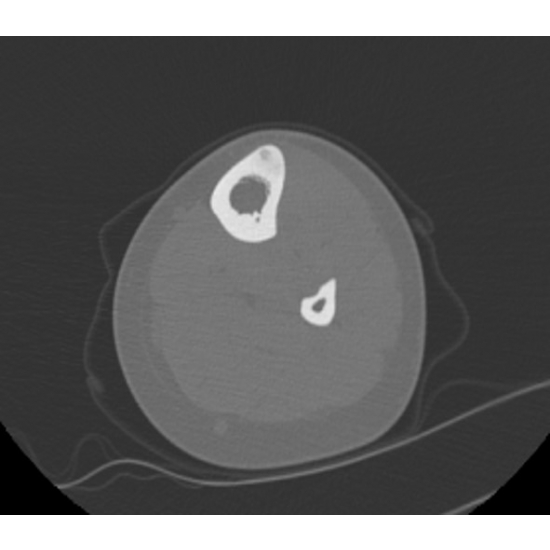

| Hoop Dreams And Bone Nightmares - Page #3 | |||